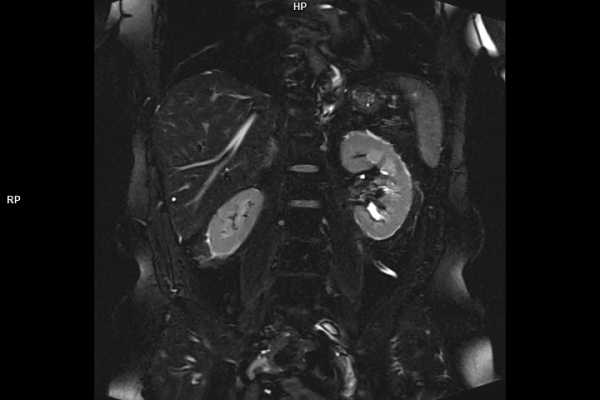

Detailbild MRT

Wir verbinden modernste Medizin mit einer Atmosphäre, in der Sie sich sicher und gut aufgehoben fühlen. Klare Abläufe, Ruhe und Zeit für Sie stehen im Mittelpunkt jeder Untersuchung. CT- und MRT-Bilder ohne Wartezeit. Mit Photon-Counting-CT und 3-Tesla-MRT setzen wir auf in Kärnten einzigartige Technologien für außergewöhnlich detailreiche Bilder und besonders präzise Diagnosen. Die schonenden Verfahren eignen sich auch für Kinder und Jugendliche. Kurze Messzeiten, große offene Geräte und ein ruhiges Umfeld sorgen für eine angenehme Untersuchung und ein gutes Gefühl von Anfang bis Ende.

Wir bieten ein breites Spektrum an Untersuchungen an, von Standarduntersuchungen der Gelenke, Organe oder großflächigen Körperregionen bis zu Spezialuntersuchungen zum Beispiel des Herzen oder der Gefäße. Zusätzlich werden Angiographien (Darstellung von Blutgefäßen), Endometriose-Abklärungen und Mamma-Untersuchungen durchgeführt. Genauere Details können Sie der MRT/CT-Übersicht und der Preisliste entnehmen, oder Sie wenden sich direkt an unser Team, das Sie gerne zur passenden Untersuchung berät.

Die MRT (Magnetresonanztomographie) arbeitet mit Magnetfeldern und Radiowellen und eignet sich besonders für Untersuchungen der Weichteile wie Gehirn, Muskeln oder Gelenke. Die CT (Computertomographie) nutzt Röntgenstrahlen und liefert schnelle, hochauflösende Bilder, insbesondere für Knochen, Lunge oder innere Organe. Die Wahl der jeweiligen Untersuchung richtet sich an das individuelle Krankheitsbild und wird bei der Überweisung festgelegt.